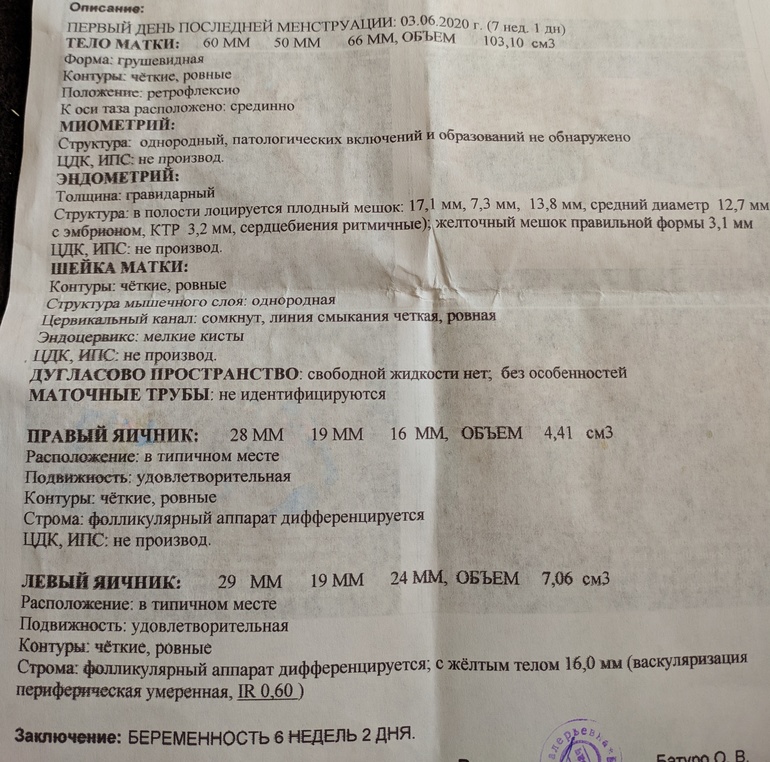

Сказали,что все хорошо, то,что отстает на 6 дней срок- это норма. По М 7+1, по УЗи 6+2 . КТР 3.2 мм. Это не мало? СБ есть, сколько не сказала,просто показала как бъется. Что то мелькнуло в ее словах про жёлтое тело, слабо работает,потом если что добавят, что- то такое я услышала, потому что я плохо слышала, только свое серцебиение в ушах от страха. Чуть не зарыдала.  говорит,можно на учёт, но я не хочу, я бы хотя бы в 10 пошла бы на учёт вставать. Эта женщина Узист хорошая, а там в ЖК все злые. Страшно к ним идти. Что дальше делать? Расслабиться на две- три недельки а потом на учёт? Что она могла иметь ввиду про жёлтое тело?

говорит,можно на учёт, но я не хочу, я бы хотя бы в 10 пошла бы на учёт вставать. Эта женщина Узист хорошая, а там в ЖК все злые. Страшно к ним идти. Что дальше делать? Расслабиться на две- три недельки а потом на учёт? Что она могла иметь ввиду про жёлтое тело?  наш малыш, пусть все будет хорошо 🙏🙏🙏🙏

Ну да,она сказала "смотри пульсирует". ) Сказала все хорошо, угрозы нет. Поэтому я жду 10 недель по М и иду ещё раз и там уже на учёт.

Не переживайте! Пупсик нагонит ещё и перегонит. У меня в 6+6 ктр был 2.9, в 8+4 уже 19. И ЖТ подросло с 18 до 22. Все у вас хорошо!